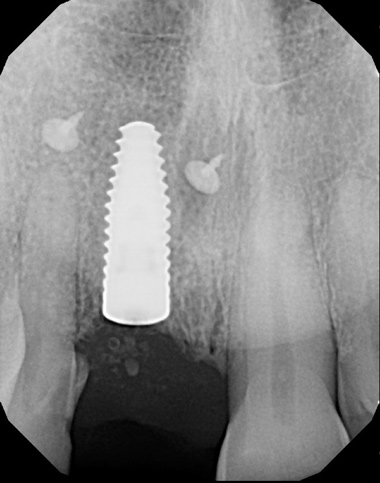

(6.) Pretreatment periapical radiograph.

Figure 6

A 56-year-old female patient was referred for the evaluation of tooth No. 8 (Figure 4 and Figure 5). A periapical radiograph indicated that the tooth had undergone apicoectomy and received an excessively long post (Figure 6), and a cone-beam computed tomography (CBCT) scan of the site revealed a lack of buccal plate bone (Figure 7).